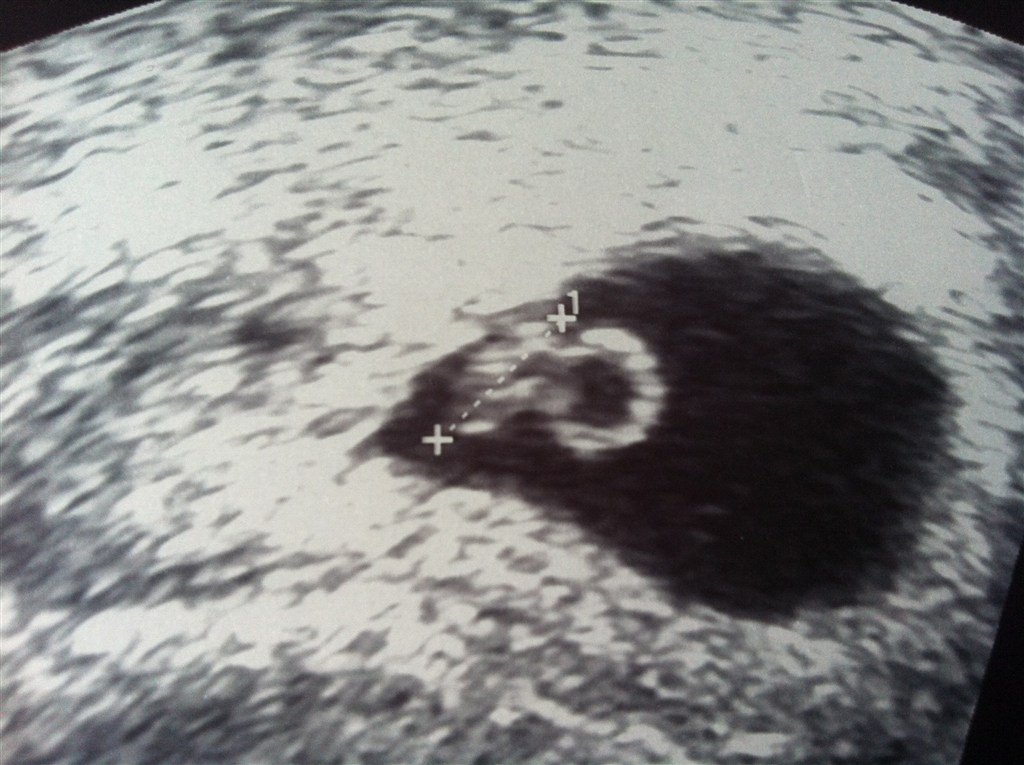

Viste en dejlig lille reje med et smukt blinkende hjerte!

Den lille bebsi har allerede nu efterabet sin storebror, da vi så ham ved samme "alder" til scanning for 2 år siden, og medbragt en flot stor blommesæk (boblen til højre for rejen).

Terminen blev rykket til den 29 December, så er idag 6+6

Ih hvor var det bare fantastisk at se dens lille hjerte galopere derud af